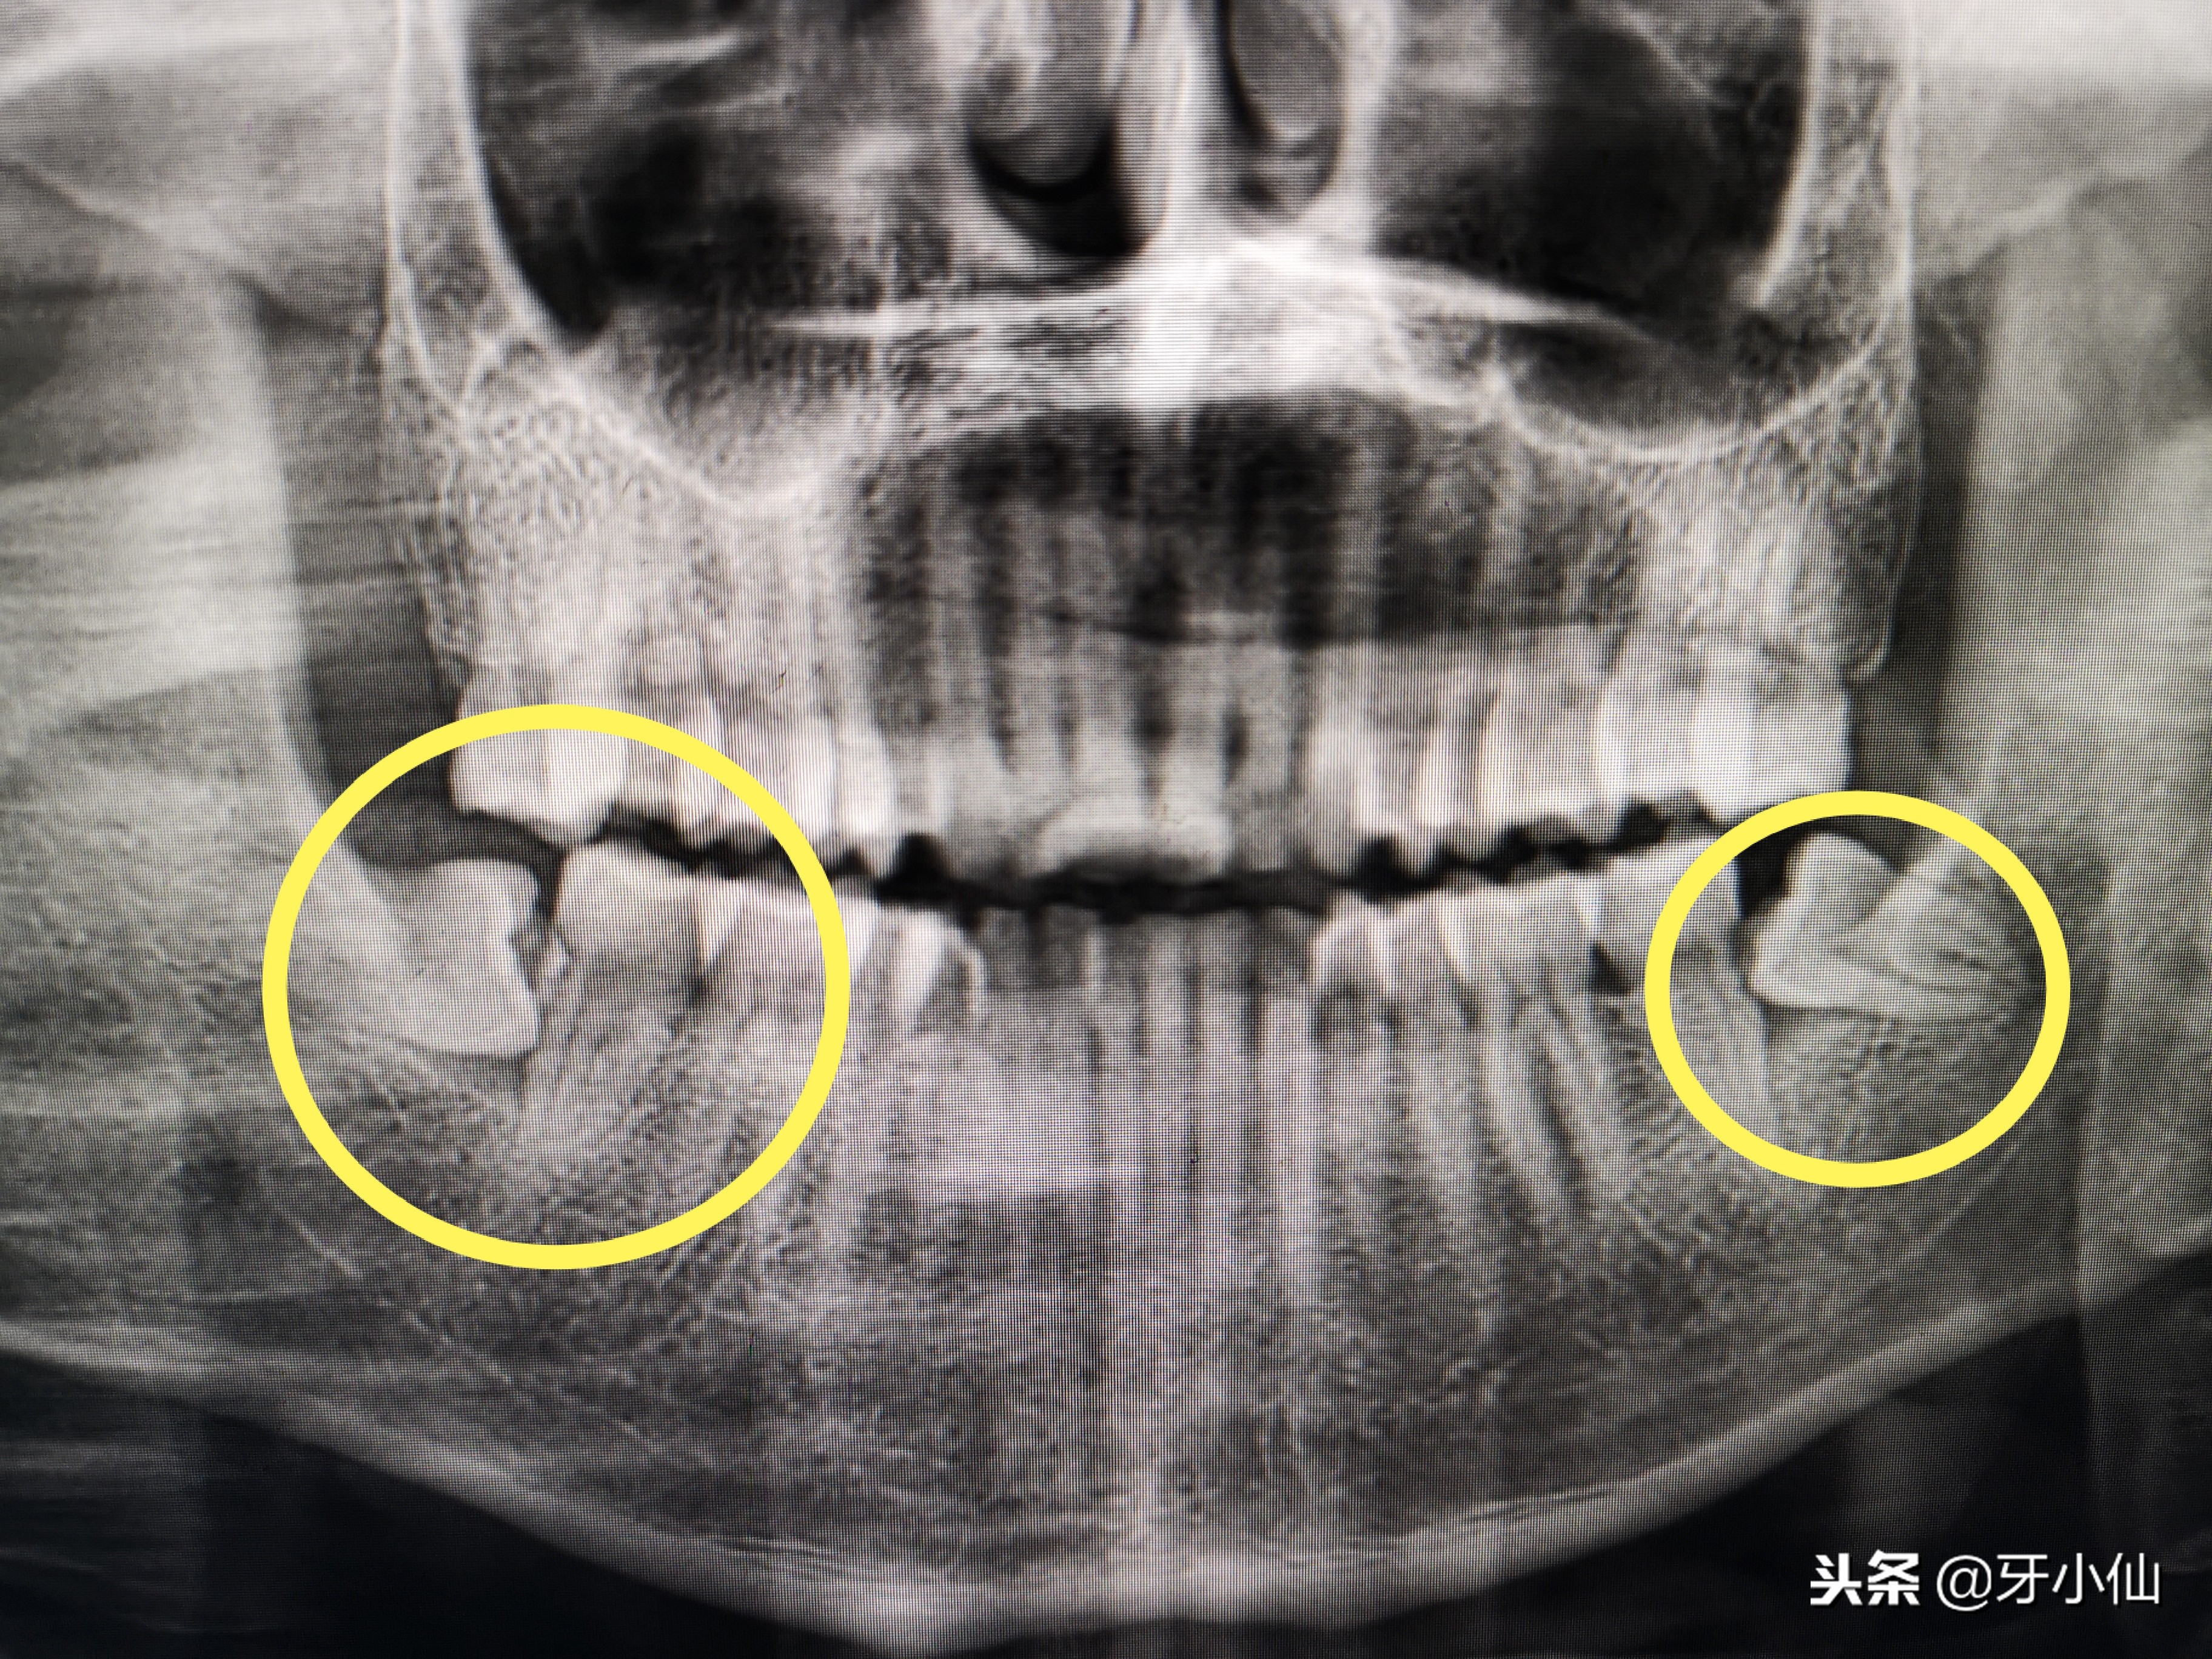

智齿需要拔除